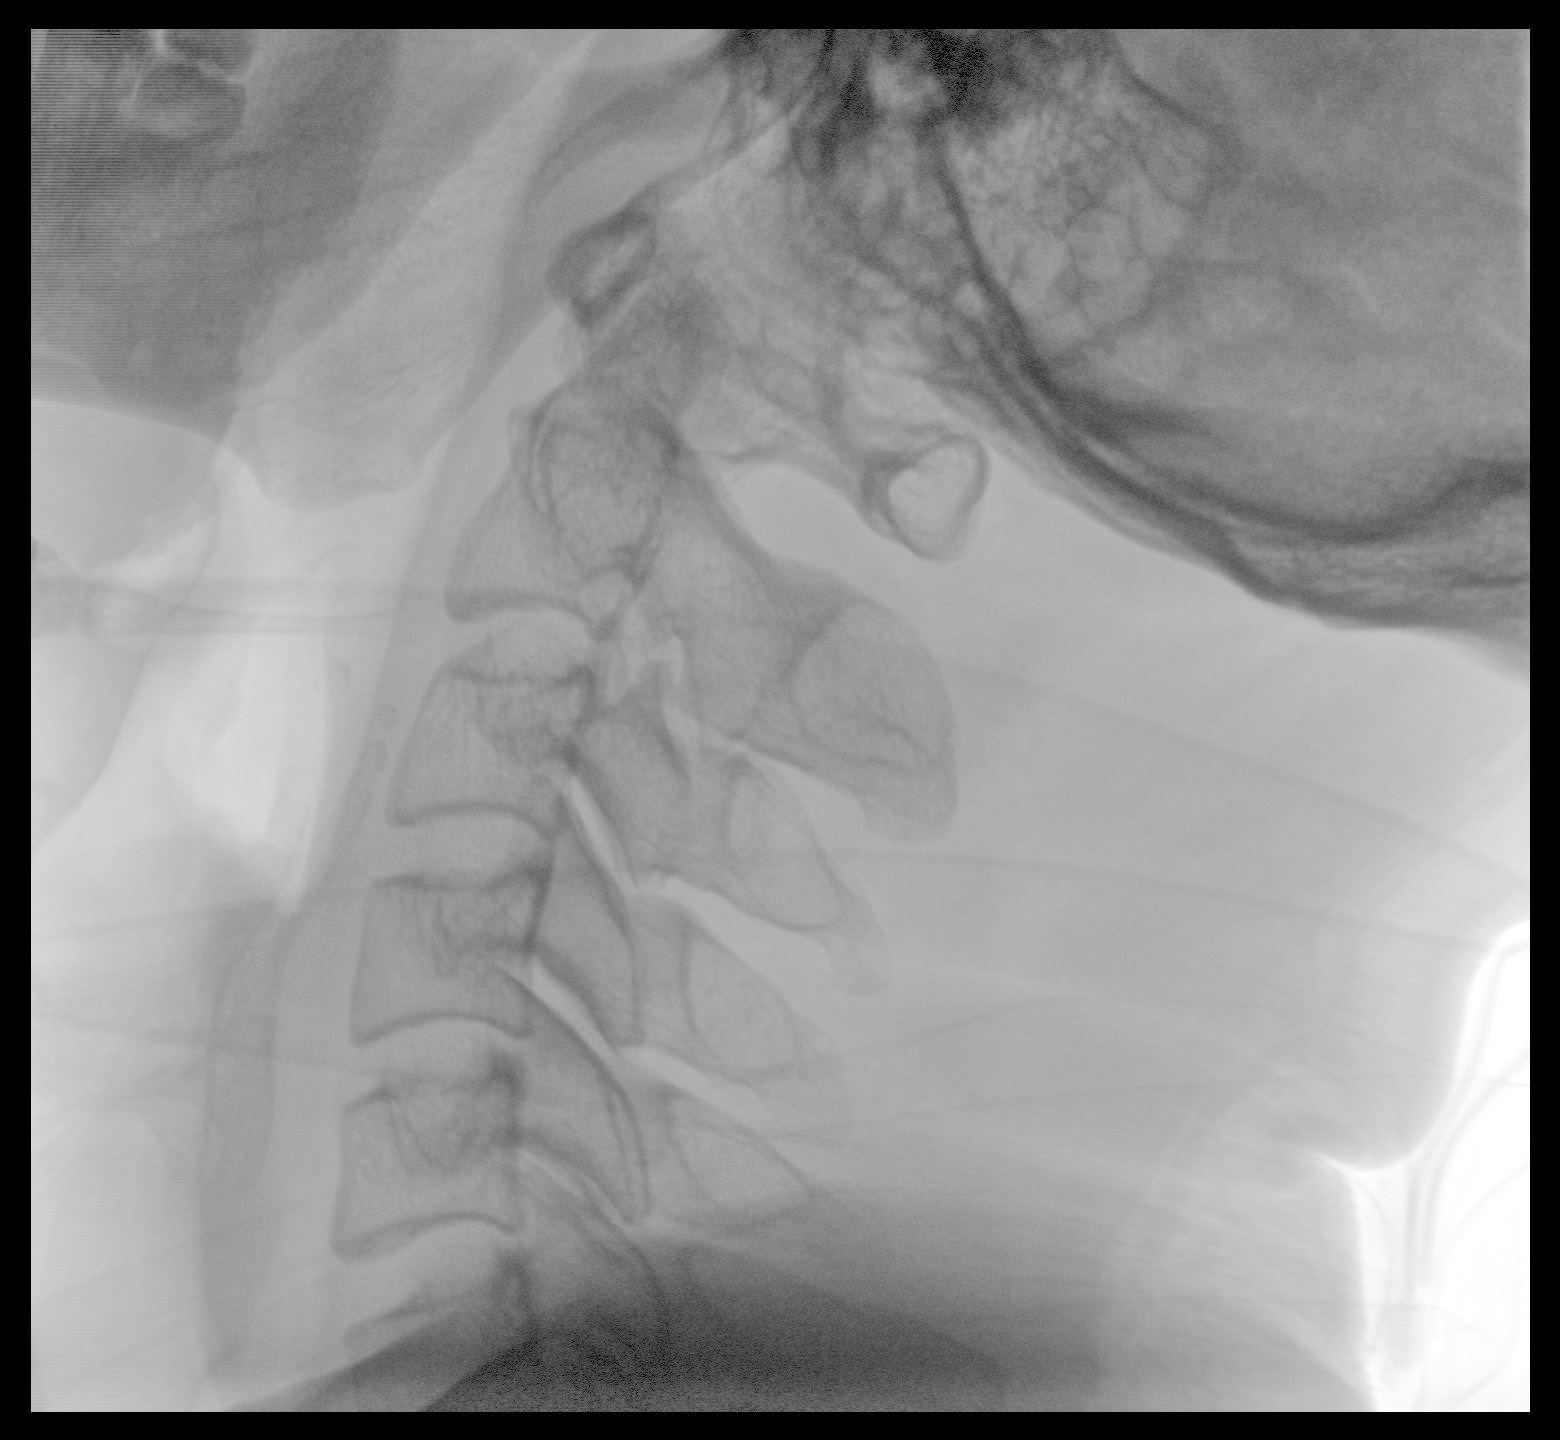

PLX118F-Plus配备了两种平板尺寸,大尺寸动态平板探测器成像面积较传统平板探测器提升了25%以上,在视野需求大的手术中,便于医生更好定位病灶点,规划手术方案,减少因视野范围不足而多次透视、点片造成的不便,不仅提高了手术效率,也减少了辐射剂量。